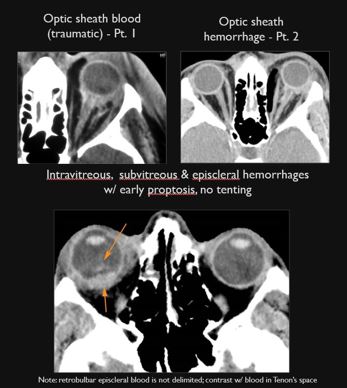

There is evidence of a subretinal, subchoroidal, subhyaloid or intravitreous hemorrhage or other fluid collection. [Yes/No]

The junctions of the optic sheath/nerve and eye are abnormal. [Yes/No]

Proptosis or enophthalmos is present. [Yes/No]

There is evidence of hemorrhage in or along the optic nerve and/or sheath. [Yes/No]